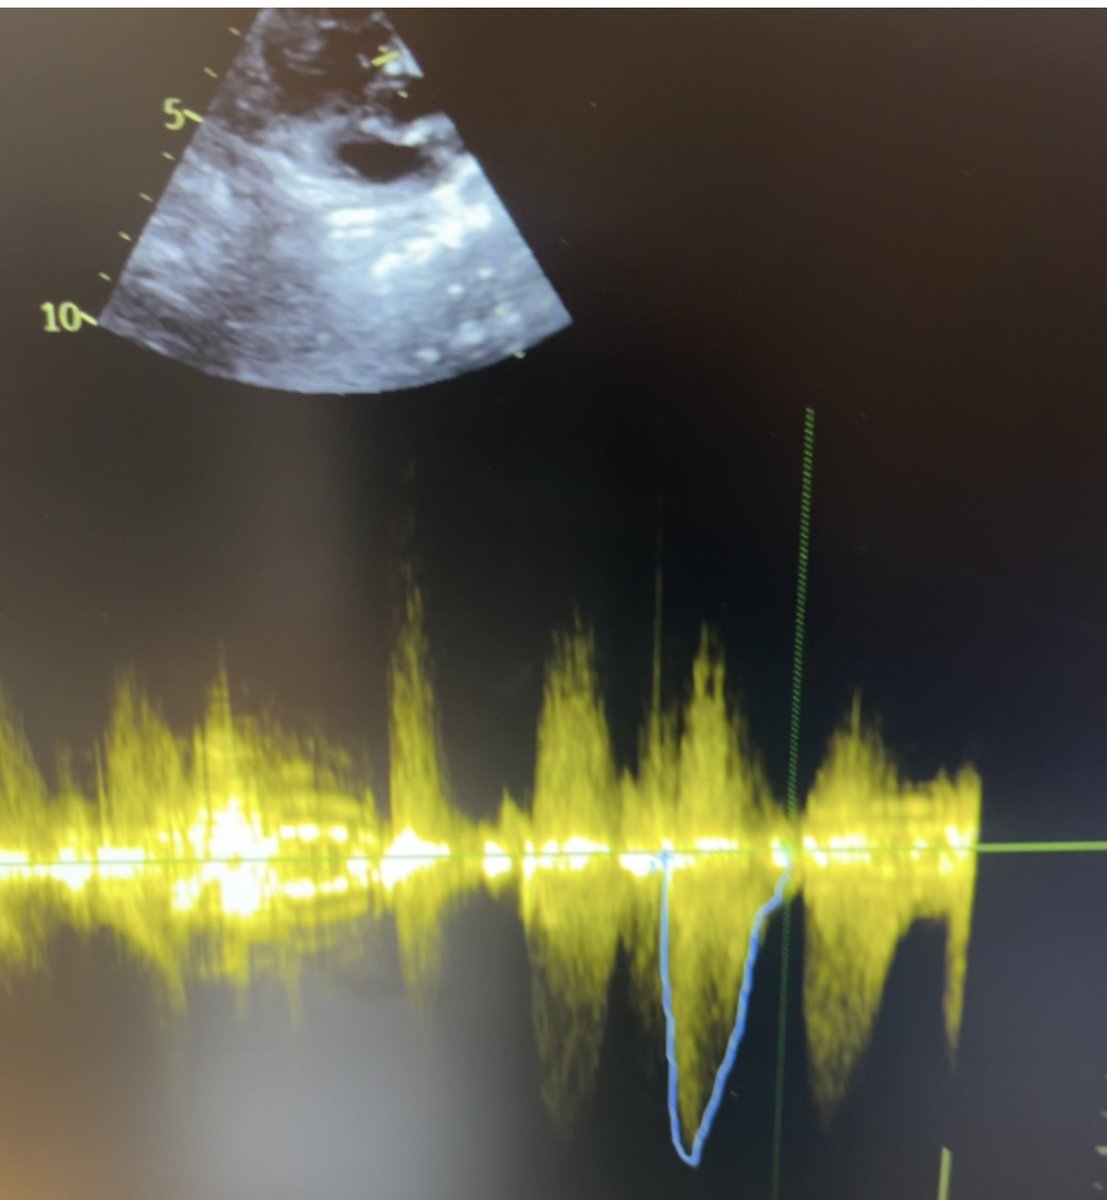

#ImageOfTheWeek by Ram Manohar Talupula and Ramesh Babu Pothineni from Aster Ramesh Hospitals, Vijayawada, India. What is the calcific mass? ow.ly/THqs50Xkag4 #cardioed